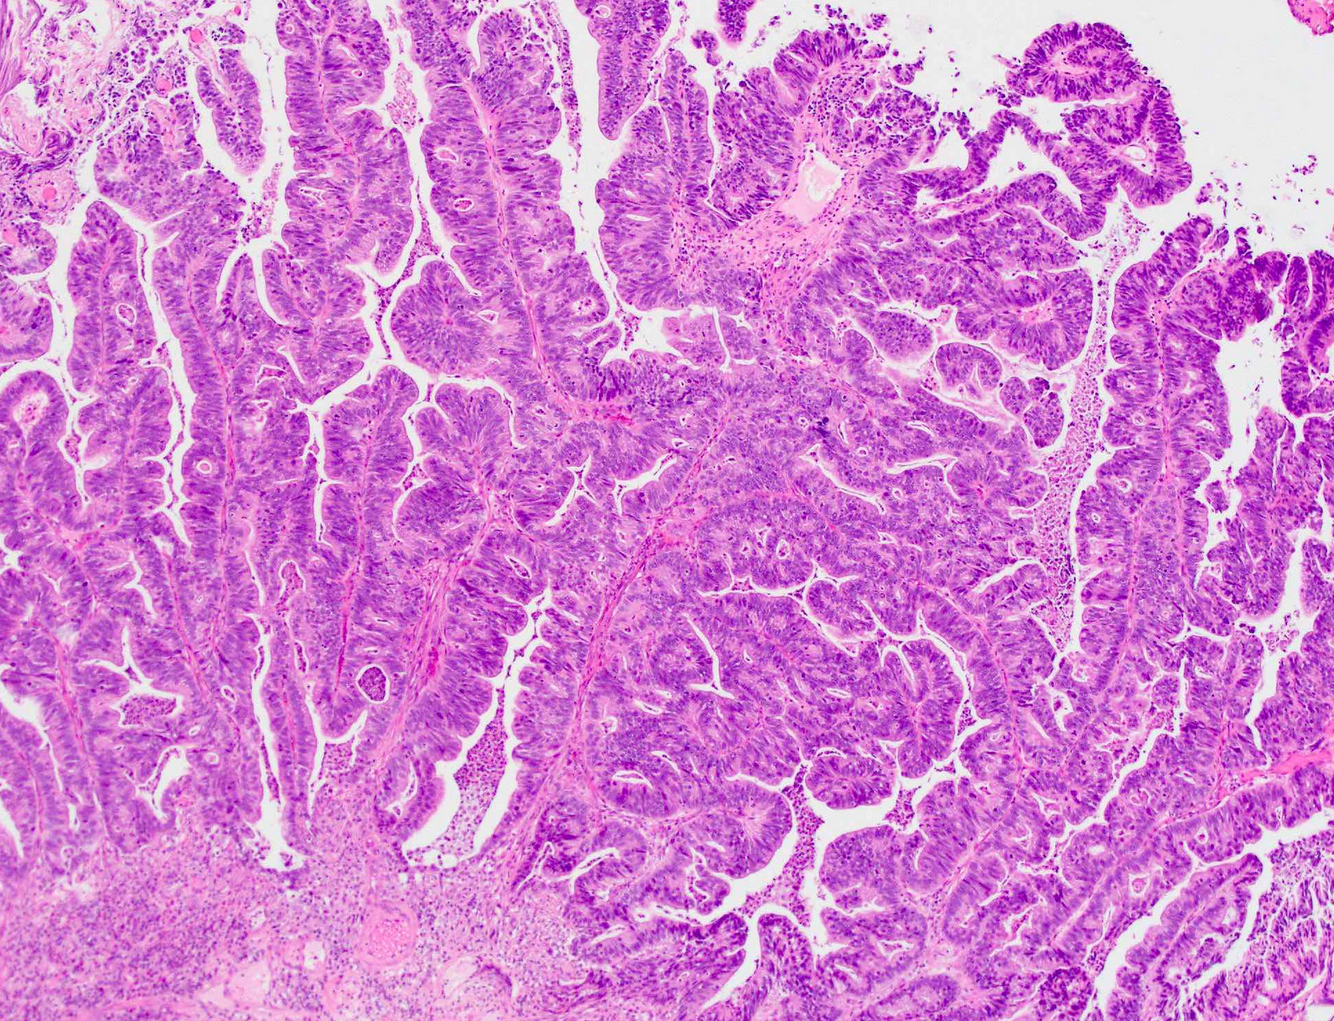

Low-grade papillary urothelial carcinoma

Thin fibrovascular cores lined by a urothelium that is thicker than normal. Still fairly well organized (most cells polarized with respect to surface). There is scattered, subtle nuclear atypia consisting of random slightly enlarged, darker nuclei, in contrast to PUNLMP (where every nucleus looks the same). Mitoses are uncommon, but should be present.

High grade papillary urothelial carcinoma

Papillary lesion lined by cells that look like CIS. May be noninvasive, but you have to look carefully for associated invasion (because it is often present!)

The urothelium is disordered with poor polarization. Nuclei are enlarged, hyperchromatic, and pleomorphic, maybe with nucleoli. Mitoses are seen at all levels of the epithelium and there is focal non-urothelial differentiation (squamous or glandular).